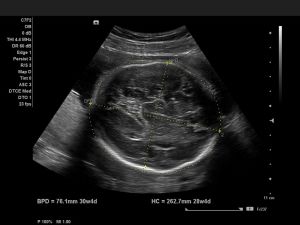

Вимірює БПР плода фахівець з УЗД. Робиться вимір в напрямку від скроні до скроні. Якщо лікар візьме неправильна відстань, не врахує, що лінія, що з'єднує контури скронь, повинна бути чітко над таламуса, то він може отримати далекі від вірних результати. Далі вимірюється лобно-потилична частина, яку вимірюють від чола до потилиці дитини.

Виконавши вимірювання БПР на УЗД, лікар порівнює їх з нормальними розмірами. Для таких порівнянь розроблені таблиці, де записані середні показники нормального БПР для кожного тижня вагітності і допустимі відхилення.

BPD - УЗД знімок, який показує біпаріетальний розмір

Розміри BPD на узі (БПР)

Майбутнім матусям під час вагітності кілька разів пропонується обстеження УЗД. Після такого обстеження лікар-узіст обов'язково видає на руки вагітним протокол дослідження, в якому розписана вся інформація про малюка, в тому числі і БПР.